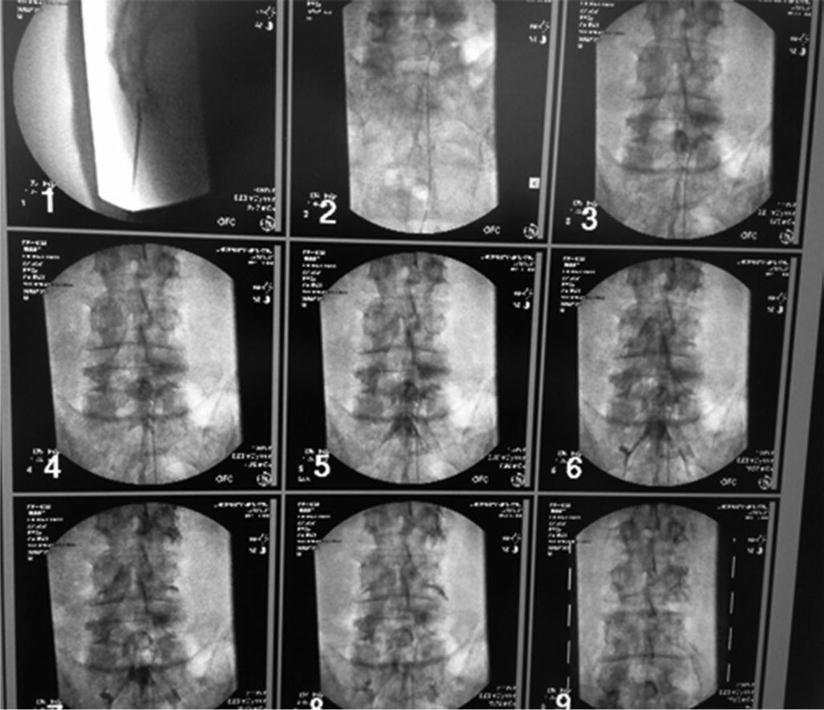

From aneskey.com

Cervical Epidural Lysis of Adhesions Anesthesia Key Cpt Code For Lysis Of Adhesions  Cpt (r) includes a number of codes which are for lysis of adhesions categorized by location. The centers for medicare & medicaid services (cms) national correct coding initiative (ncci) policy manual for medicare services provides the following guidance on reporting. Cpt 58740 is used to describe the surgical procedure of lysis of adhesions, specifically around the fallopian tubes and ovaries.. Cpt Code For Lysis Of Adhesions.

Cervical Epidural Lysis of Adhesions Anesthesia Key Cpt Code For Lysis Of Adhesions  Learn how to code and bill for lysis of adhesions procedures, such as enterolysis, salpingolysis, or ovariolysis, with select health plans. Cpt 58740 is used to describe the surgical procedure of lysis of adhesions, specifically around the fallopian tubes and ovaries. A patient with chronic pelvic pain and severe. The centers for medicare & medicaid services (cms) national correct coding. Cpt Code For Lysis Of Adhesions.